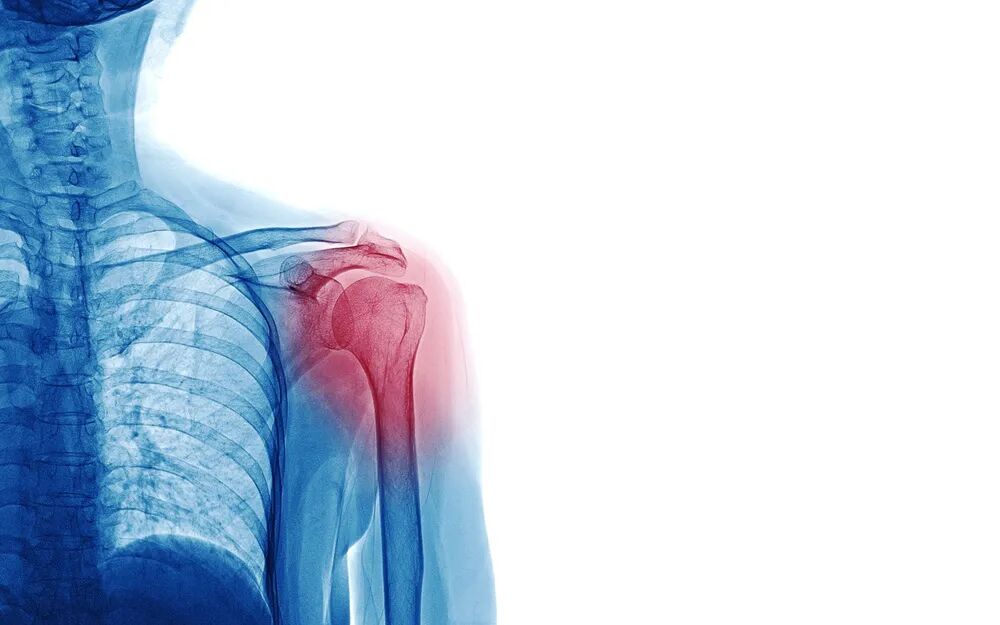

颈部疼痛是所有颈椎病中最常见的首发症状。通常情况下,颈部疼痛多合并颈项僵硬、活动不利的症状。

疼痛的性质多为钝痛、刺痛或酸胀痛,可在早晨起床时多见,或低头工作后明显加重。

疼痛的范围:自颈椎向下呈扇形分布,如上背部肩胛骨区域及肩臂部出现疼痛。

颈椎病中有六至七成的患者会出现肩、臂、手部的疼痛和麻木症状。这些部位的疼痛可呈针刺样痛、酸胀痛、烧灼样痛。严重者会出现从颈背部向手臂、手指放射的放电样疼痛,甚至咳嗽、打喷嚏或深呼吸都会加重以上症状。

麻木感主要出现在肩部外侧的三角肌区、上臂外侧及手指等区域。颈椎病患者的手指麻木症状具有一定的特征性,要么表现为桡侧麻木(包括拇指、食指、中指及半个无名指),要么表现为尺侧麻木(包括小指、半个无名指)。